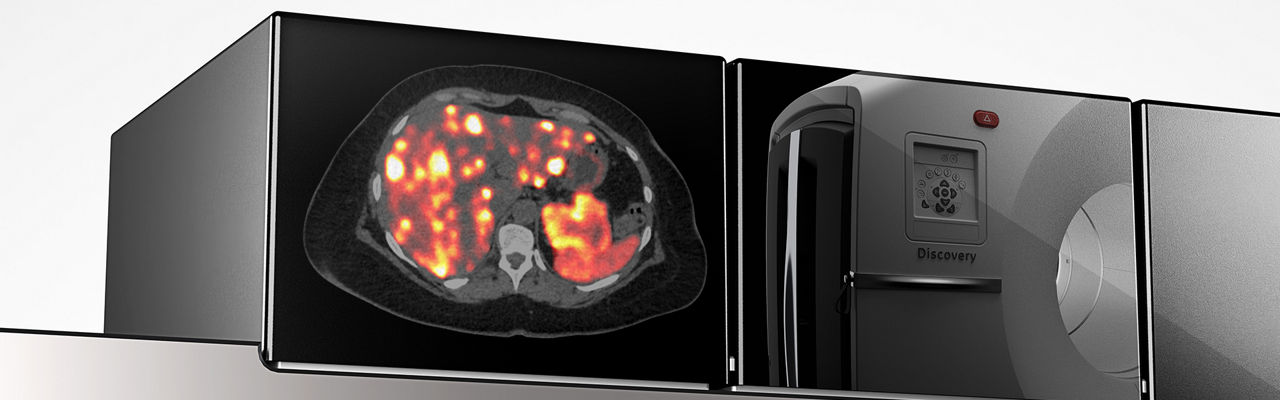

Discovery MI Gen 2

Eine neue Generation der weltweit ersten digitalen PET/CT-Plattform.

Mit der bahnbrechenden digitalen PET-Technologie, der neuesten diagnostischen CT und der fortschrittlichen quantitativen Software wurde Discovery™ MI entwickelt, um Ihre Forschung zu beschleunigen und Ihre klinische Arbeit zu verbessern. Der Discovery MI Gen 2 ist die nächste Generation dieser unglaublichen Bildgebungstechnologie. Das System wurde so konzipiert, dass es eine beeindruckende Abdeckung von 30 Zentimetern erreicht und mit einem diagnostischen CT kombiniert ist, das eine Deep-Learning-basierte Bildrekonstruktion ermöglicht. Die durchdachte Entwicklung ermöglicht zudem effizientere Abläufe für den MTRA. Willkommen bei einer neuen Generation digitaler PET/CT.